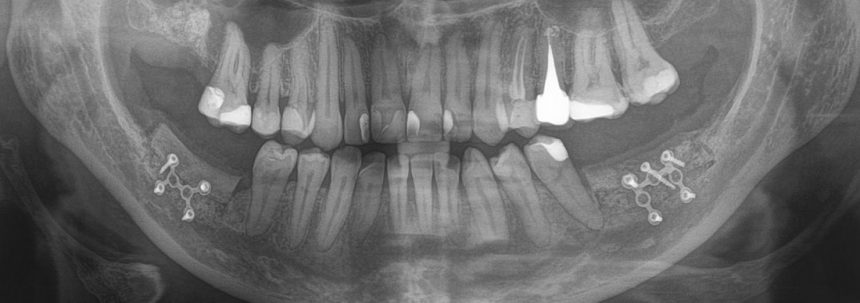

После операции мы делаем контрольные снимки. Это может быть ортопантомография:

или конусно-лучевая компьютерная томография. Как вам больше нравится.

Результат остеопластики методом остетотомии мы можем оценить уже через 4 месяца. Перед этим сделаем контрольные снимки (слева «до», справа «через 4 мес»):